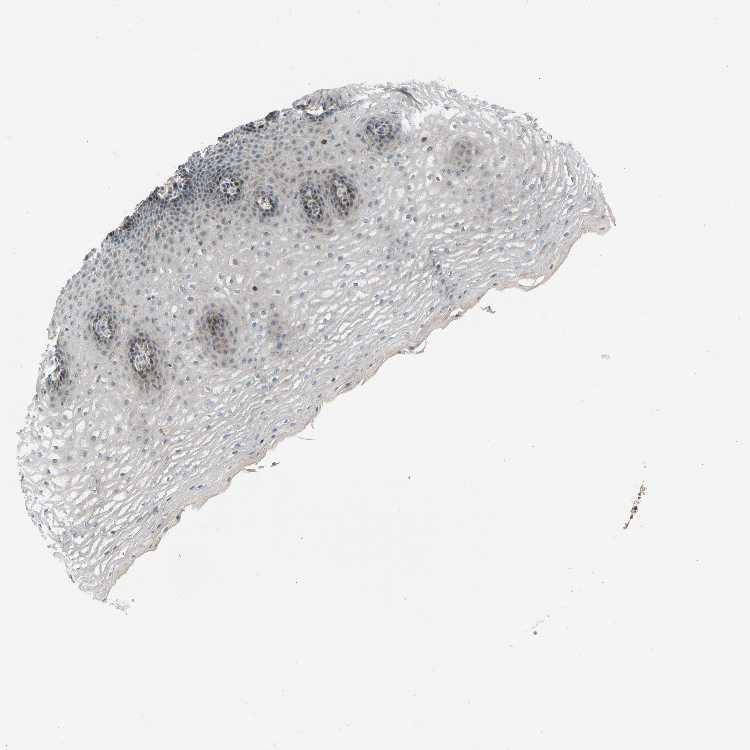

ESOPHAGUS - Antibody stainingi

Antibody staining in the annotated cell types in the current human tissue is reported as not detected, low, medium, or high, based on conventional immunohistochemistry profiling in selected tissues. This score is based on the combination of the staining intensity and fraction of stained cells.

Each image is clickable and will lead to virtual microscopy that enables deeper exploration of all samples and also displays staining intensity scores, fraction scores and subcellular localization as well as patient and tissue information for each sample.

Antibody HPA020080Antibody HPA020299

Squamous epithelial cells LowHigh